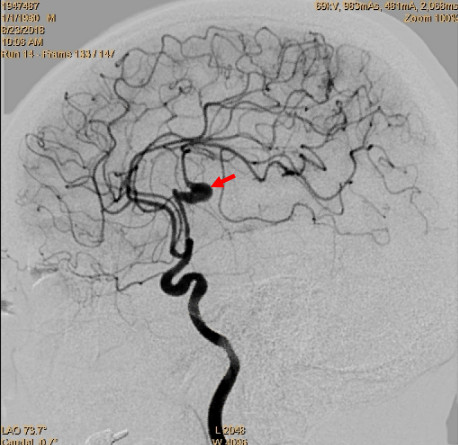

栗超跃教授颞浅动脉大脑中动脉m3搭桥术颅内蛇形动脉瘤切除并血管置换